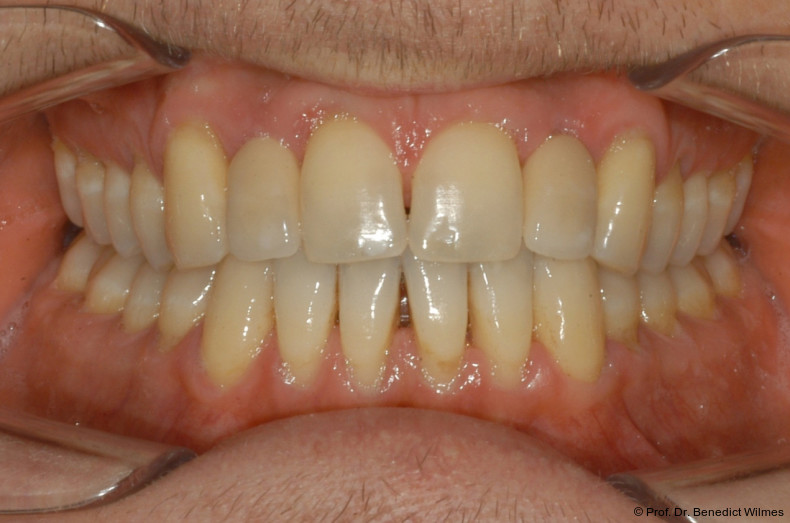

Ein 14-jähriger Patient wurde bei Aplasie der beiden oberen seitlichen Schneidezähne mit dem Ziel der beidseitigen Lückenöffnung kieferorthopädisch therapiert (Abb. 1a+b). Zum Ende der kieferorthopädischen Behandlung wurden zwei Miniimplantate in Regio 2er als temporärer Zahnersatz inseriert (Benefit System, PSM, 2 x 13 mm, Abb. 2a+b). Nach Abdrucknahme wurden Kronen auf den Peek-Abutments modelliert und diese mit Kunststoff auf die Abutments geklebt (Abb. 3a–d). In den Abbildungen 3 und 4 sind die klinischen und röntgenologischen Nachkontrollen innerhalb der nächsten achteinhalb Jahre dokumentiert. Man erkennt einen sowohl in der Höhe als auch in bukkopalatinalen Breite verbleibenden gesunden Knochen ohne Anzeichen einer Atrophie. Im Alter von 23 Jahren wurden die definitiven Implantate ohne die Notwendigkeit einer Augmentation eingesetzt (Abb. 5) und nach Einheilung prothetisch versorgt (Abb. 6a–e und Abb. 7a–c).

Bei einer elfjährigen Patientin fehlten bei Zustand nach Frontzahntrauma im Alter von neun Jahren beide oberen mittleren Schneidezähne (Abb. 8a+b). Als temporärer Ersatz wurden Miniimplantate (Abb. 9, 2 x 13 mm) eingesetzt und Kronen im Labor angefertigt, welche auf den Miniimplantaten verschraubt wurden (Abb. 10a+b). Die Miniimplantate wurden im Alter von 19 Jahren, also nach achtjähriger Nutzung (Abb. 11a+b), durch dentale Implantate ersetzt.